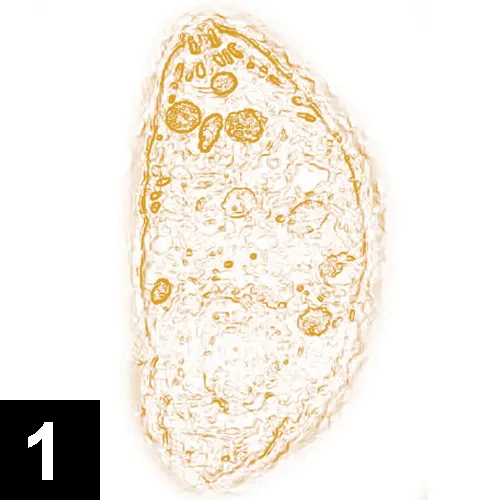

A microscopic view of a single-celled organism, displaying an elongated shape with a textured surface and various internal structures. The organism is stained in shades of orange, highlighting its cellular components against a bright background.

Image 2. Neospora caninum infection